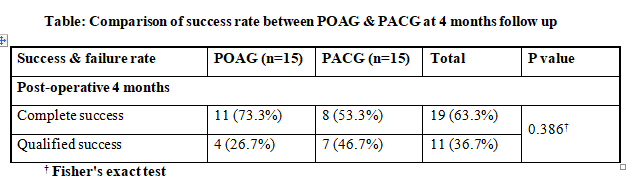

similar group over a 3-year period reported significant improvement in BCVA in ACG compared to OAG group, attributed to a higher number of cataract surgeries performed in the ACG group(9). Complete success was attained in 63.3%

patients and qualified success in 36.7%.

More POAG trabeculectomy were completely successful at 73.3% compared to 53.3% PACG cases, however the inter group difference was Not Significant. Maheshwari D et al have also reported higher success rates for trabeculectomy in

OAG at 68% compared to 55 % in ACG, over a longer follow up of 3 years8. They attributed this to more postoperative complications in PACG particularly cataract extraction resulting in poor IOP control(9). Sihota R on the other

hand with a longer follow-up of 10-year, reported similar success rates of trabeculectomy in PACG and POAG(10). A life-table analysis in a Japanese population also showed comparable 5-year control rates between POAG and PACG

eyes, with no racial differences in Asians and Caucasians(10). The current study required bleb needling to revive bleb in 2 cases of POAG group and one case of PACG.